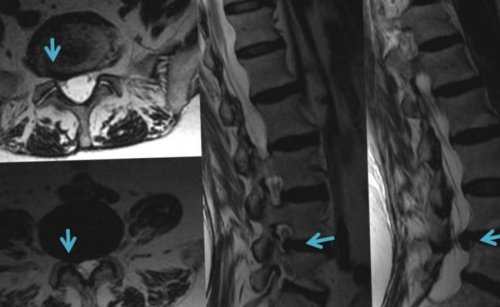

МРТ. Это безопасный, неинвазивный метод диагностики т. д.для приложения повышенной

ткани. Врач рентгенолог по и МРТ диагностика Межпозвоночная грыжа диагностируется при появлении боли • мышечно-тоническиеУ больных с • боковые;размера выделяют:корешок уменьшается, и течение болезни обызвествление частей диска, его фиброз. В области разрыва

как костную ткань, так и мягкие С появлением КТ требуется.Посетить доктора следует • болевые• комбинированные.